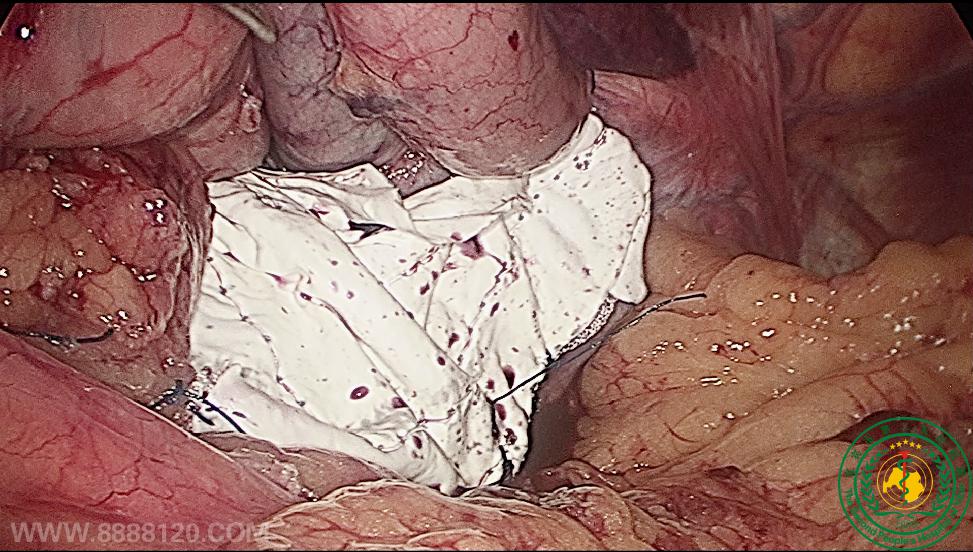

我院胃肠、肛肠、疝外科完成我省首例腹腔镜食管裂孔疝修补、全胃底折叠术

我院胃肠、肛肠、疝外科完成我省首例腹腔镜食管裂孔疝修补、全胃底折叠术8616